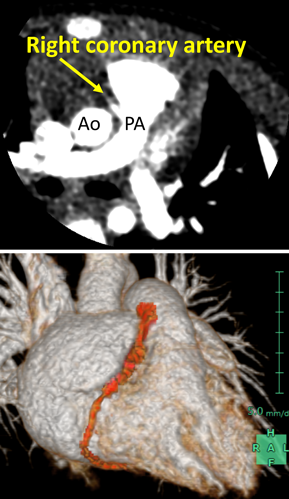

体重増加不良の精査に行った心臓超音波検査が診断につながった右冠動脈肺動脈起始Anomalous Origin of the Right Coronary Artery from the Pulmonary Artery Diagnosed by Echocardiography Performed for Close Examination of Poor Weight Gain